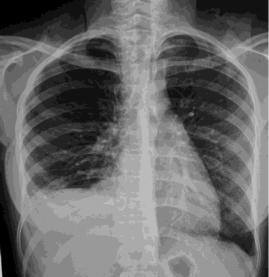

Mesenchymal Hamartoma of the Liver (MHL) is a rare benign hepatic pediatric tumor of infancy with approximately 20% of cases diagnosed during the neonatal period, typically presenting as an enlarging abdominal mass. Rare acute complications such as intralesional bleeding and infection can lead…...